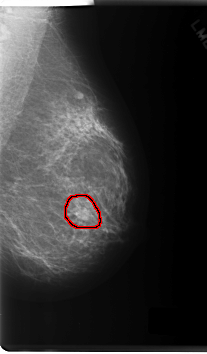

C_0165_1.LEFT_MLO

LEFT_MLO LINES 6016 PIXELS_PER_LINE 3504 BITS_PER_PIXEL 12 RESOLUTION 50 OVERLAY

FILE: C_0165_1.LEFT_MLO.OVERLAY

TOTAL_ABNORMALITIES 1

ABNORMALITY 1

LESION_TYPE MASS SHAPE ROUND MARGINS SPICULATED

ASSESSMENT 5

SUBTLETY 5

PATHOLOGY MALIGNANT

TOTAL_OUTLINES 1

BOUNDARY